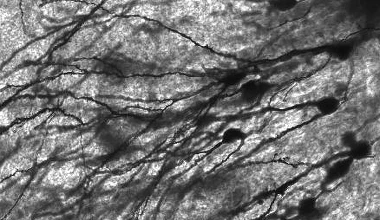

Nauka

Nanocząsteczki w mózgu